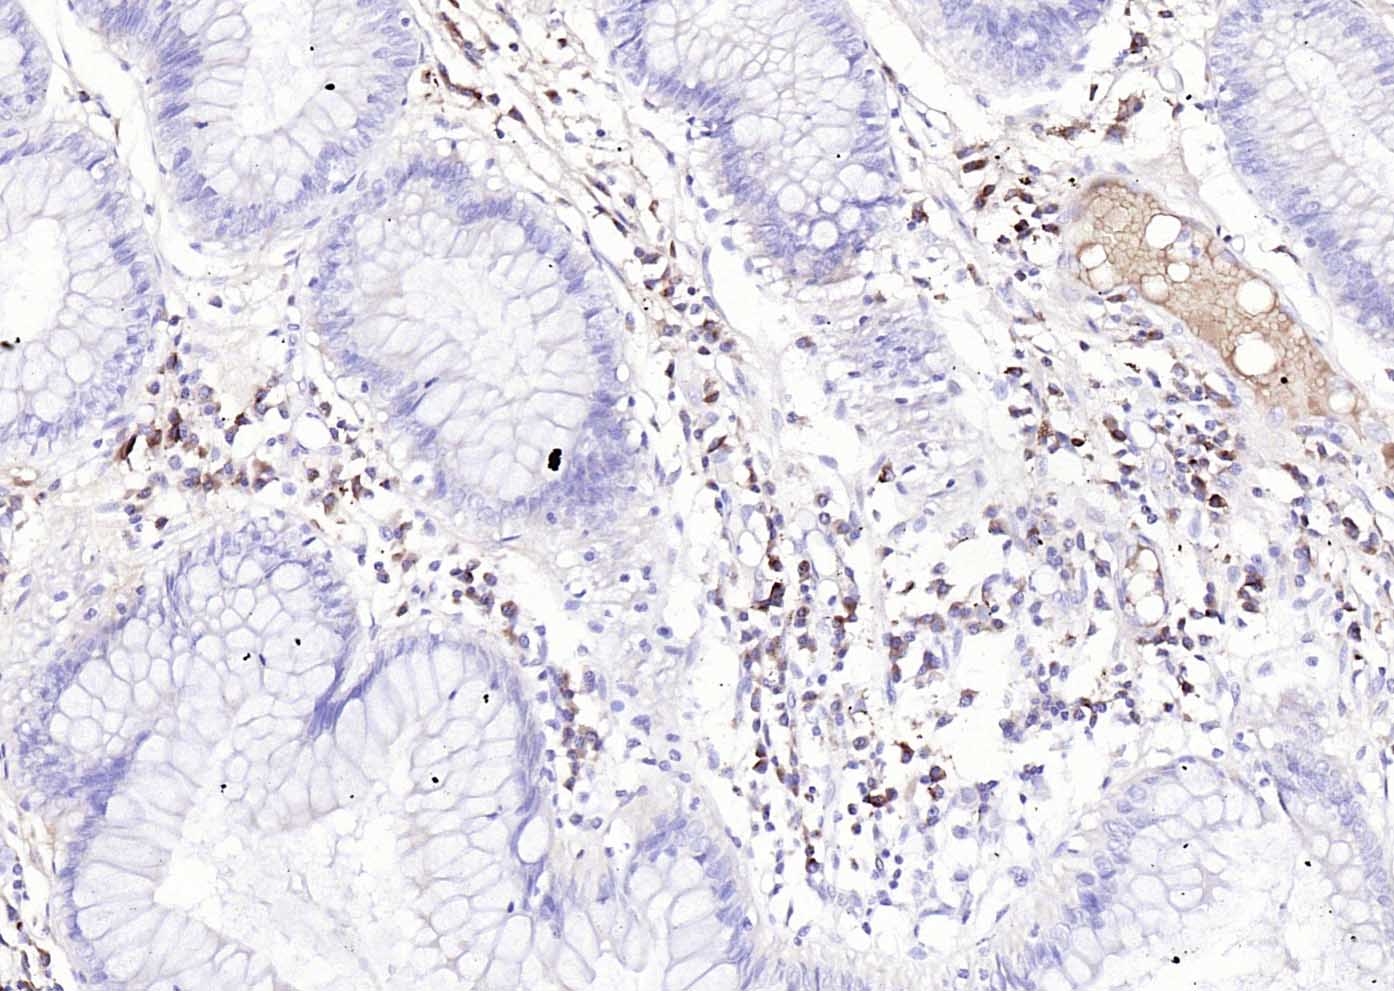

兔抗人IgG-Fc段抗体-bs-0365R兔抗人IgG-Fc段抗体-bs-0365R兔抗人IgG-Fc段抗体-bs-0365R兔抗人IgG-Fc段抗体-bs-0365R

产品应用: Isotype Control, Blocking Assay, etc., Conjugate-Dependent.

交叉反应: Human